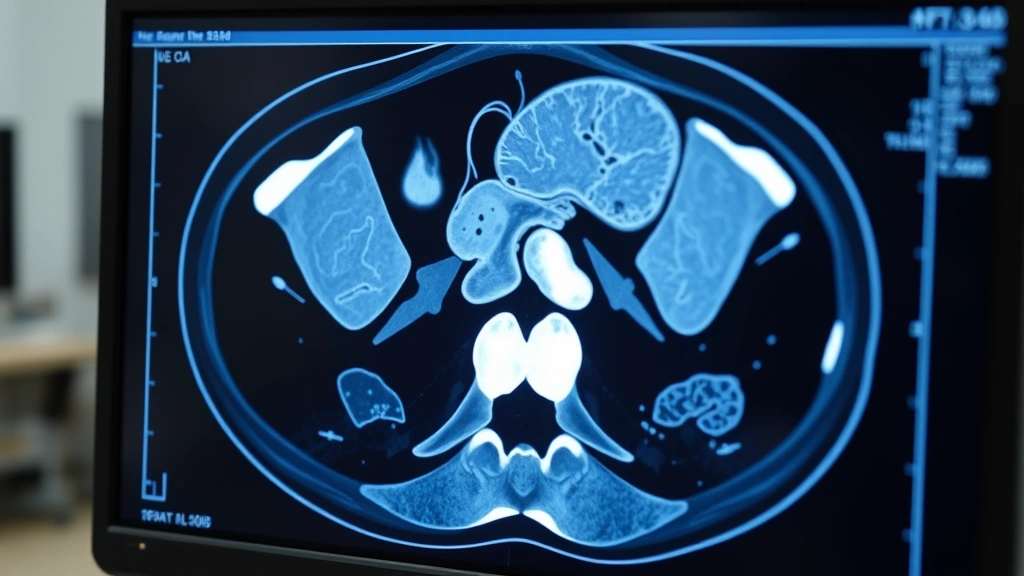

The actual scan itself takes maybe 10 to 15 minutes. You go in, they shoot X-rays from multiple angles, create a 3D image, and you’re done. But here’s what most people don’t realize: the technician who runs the machine isn’t the person interpreting it. A radiologist—a doctor specially trained in reading medical images—has to review those pictures and write up a report.

Several things can stretch your wait time beyond the standard 24-72 hours. First, complexity. A simple chest X-ray comparison takes minutes. A full abdominal CT with contrast where the radiologist is looking for subtle lesions? That’s 20-30 minutes of careful review per scan.